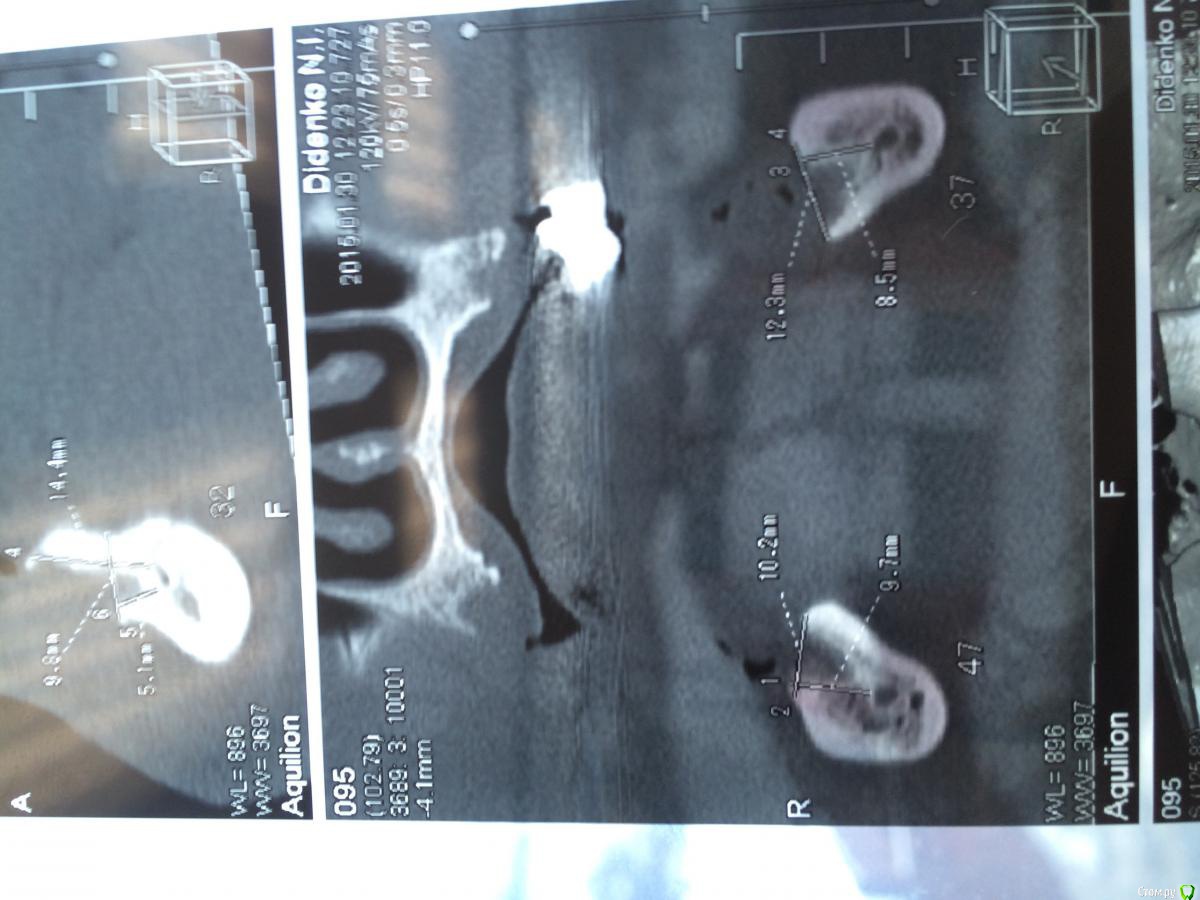

urseva19.05.10 Опубликовано 31 января, 2015 Поделиться Опубликовано 31 января, 2015 Коллеги, в каких позициях на ваш взгляд целесообразнее поставить имплантаты желательно без НКР ( пациент ограничен во времени) что бы в последствии протезироваться съемным протезом на локаторах? На верх не смотрите там все ясно Спасибо! Ссылка на комментарий

Alejandro Опубликовано 31 января, 2015 Поделиться Опубликовано 31 января, 2015 В области 36,46 толщина альвеоляра какая? Ссылка на комментарий

urseva19.05.10 Опубликовано 31 января, 2015 Автор Поделиться Опубликовано 31 января, 2015 10,5 и 9,2 соответственно Ссылка на комментарий

syrovovec Опубликовано 31 января, 2015 Поделиться Опубликовано 31 января, 2015 Ставьте в межментальное 2 или 4, как вам больше нравитсяPs фотки очень неудобно смотреть, срезы замеры не информативные 1 Ссылка на комментарий

Alejandro Опубликовано 31 января, 2015 Поделиться Опубликовано 31 января, 2015 Я бы поставил два межментально в области клыков, и два в области шестёрок тогда. Можно не сильно параллелить - на локаторах это прощается. Ссылка на комментарий

kriokov Опубликовано 31 января, 2015 Поделиться Опубликовано 31 января, 2015 1. выравнивайте гребень2. Позиции 34 , 32, 42, 44, если болты позволяют их субкрестально поставить , то притопите, и ушиться бы двурядно, Ссылка на комментарий

urseva19.05.10 Опубликовано 1 февраля, 2015 Автор Поделиться Опубликовано 1 февраля, 2015 1. выравнивайте гребень2. Позиции 34 , 32, 42, 44, если болты позволяют их субкрестально поставить , то притопите, и ушиться бы двурядно, 1. Всё-таки считаете без НКР не обойтись?2. С 32,42 понятно, а если в области 36,46 установить не будет ли лучше фиксация протеза, да и условия вроде позволяют. Как думаете? Ссылка на комментарий